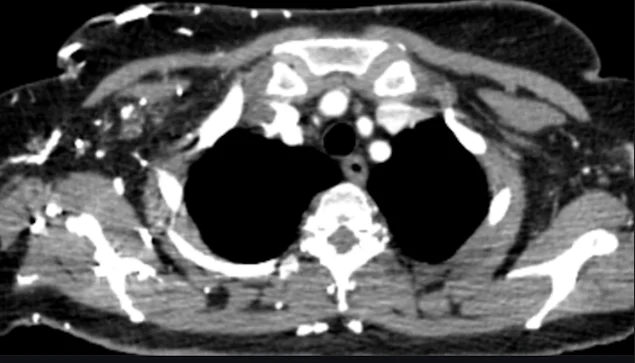

Figure 1. Axial Contrast – Enhanced CT of the Thoracic Inlet

This axial contrast – enhanced CT image at the level of the thoracic inlet demonstrates an intraluminal filling defect within the subclavian vein, consistent with acute subclavian venous thrombosis.

Key Radiologic Findings:

- The affected subclavian vein appears partially opacified, with a central low – attenuation (hypodense) filling defect, indicating thrombus.

- There is asymmetry compared to the contralateral side, where the vein is normally enhanced with contrast.

- Mild venous distension may be present, suggesting acute obstruction.

- Surrounding soft tissues may show subtle edema, supporting an acute process.

Clinical Significance:

These findings confirm upper extremity deep vein thrombosis (UEDVT) involving the subclavian vein.

This is a clinically important source of pulmonary embolism, particularly in patients with risk factors such as central venous catheterization or thoracic outlet syndrome.

Early detection on CT is critical for prompt anticoagulation and prevention of embolic complications.

Diagnostic Contribution:

This image plays a key role in:

- Identifying the primary thrombotic source

- Supporting the diagnosis of thromboembolic disease

- Guiding further evaluation for pulmonary embolism via CT pulmonary angiography